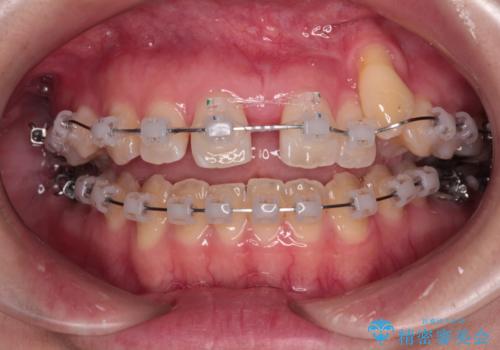

急速拡大装置 狭い上顎骨を拡大してワイヤー装置で八重歯を短期間治療

- クリアブラケット

- 上顎の八重歯やデコボコを気にして来院された患者様です。

上顎歯列が狭窄していたため、急速拡大装置により上顎骨を側方に拡大しながら、ワイヤー装置にて矯正治療を行うこととしました。

上顎骨を拡大することで、八重歯やデコボコを歯列に収めることができ、下顎の歯が外に位置していた奥歯の咬み合わせも改善することができました。

スペースも短期間に獲得できるため、1年程度で治療を終えることができました。